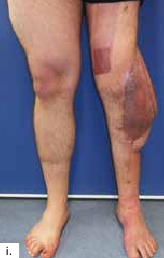

Ein 28-jähriger Motorradfahrer kollidierte mit einem Pkw und erlitt eine Defektfraktur der linken proximalen Fibula und einen Verlust der lateralen Femurkondyle inklusive des lateralen Bandapparates unter einem extrem großen Weichteildefekt (Abb. 2a u. b). Nach multiplen auswärtigen Debridements wurde nach Zuweisung ins eigene Haus interdisziplinär besprochen, die Extremität mit einer Kniegelenkprothese und einer plastisch-chirurgischen Defektdeckung zu erhalten. In einem ersten Schritt wurde ein kontralateraler Tensor-fasciae-latae-(TFL-) Lappen umschnitten („flap delay“), um ihn in seiner gesamten Länge vom Beckenkamm bis zum Knie heben zu können. Eine Woche später erfolgte die Konstruktion der fabrizierten Chimärlappenplastik durch Hebung des osteofasziokutanen TFL-Transplantats inklusive eines vaskularisierten Beckenkammblocks und der mikrovaskuläre Anschluss End-zu-End an den Serratusabgang der A. thoracodorsalis des rechten muskulokutanen M.-latissimus-dorsi-Lappens (Abb. 2c). Dieses sehr große zweiblättrige Lappenmodul wurde anschließend End-zu-End an die Vasa gastrocnemia lateralis anastomosiert und die vaskularisierten Einzelkomponenten wie folgt verteilt: Der Beckenkammblock fungierte als laterale Kondylenaugmentation, um den Sitz einer späteren Knieendoprothese zu optimieren; die Faszia lata wurde zur Stabilisierung von diesem Block transossär an die verbleibende Fibula und das laterale Tibiamassiv genäht (Abb. 2d). Die ausgedehnten Lappenplastiken dienten zum Defektverschluss, gemeinsam mit zusätzlichen Spalthauttransplantaten (Abb. 2e). Nach sechswöchiger Abheilung im Fixateur externe erfolgten der Umschulungsbeginn und die Mobilisation an Unterarmgehstützen mit Fußsohlenteilkontakt.

Sechs Monate später konnte bei solide eingeheiltem Knochenblock (Abb. 2f) eine teilgekoppelte Kniegelenkprothese implantiert werden, deren Bedeckung in der Folge durch die ausreichend dimensionierten Lappenplastiken unproblematisch war (Abb. 2g u. h). Der Patient erzielte nach Rehabilitationsmaßnahmen eine vollständige Belastungsfähigkeit bei freier Kniegelenkbeweglichkeit und solide verheiltem Integument (Abb. 2i u. j).